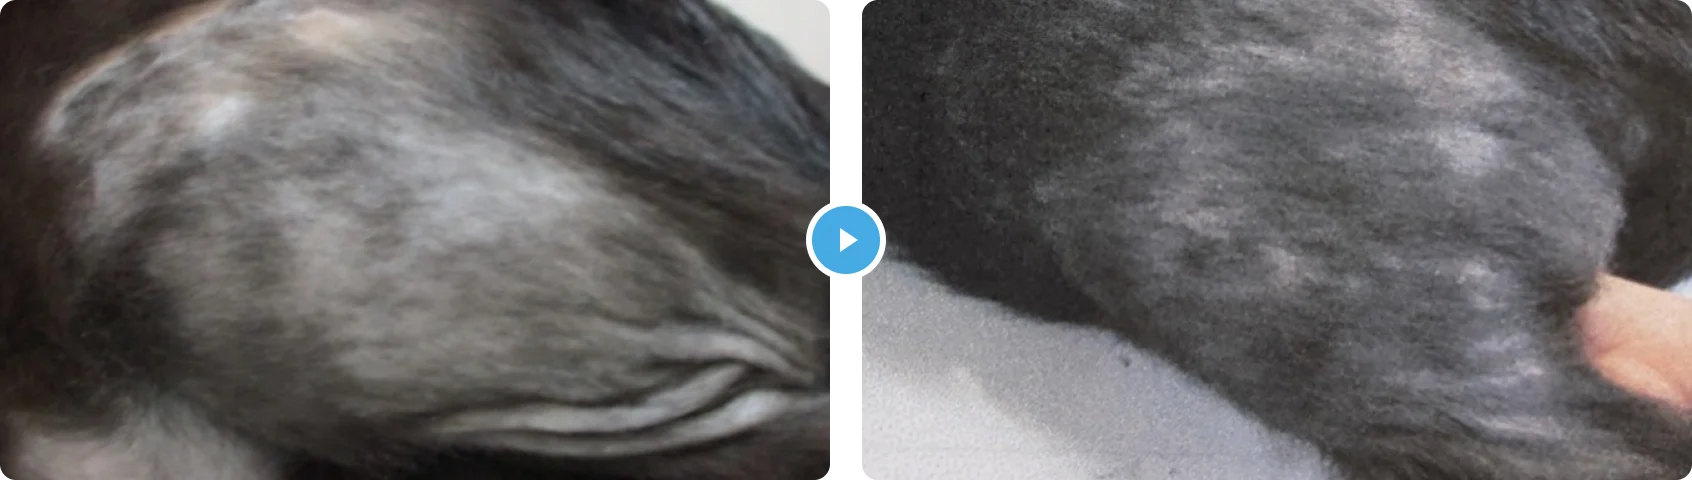

がいしょうせいだつもう 外傷性脱毛

- 症状の説明

- 治療の内容

やや緩和するものの、改善はなく脱毛は広がっていくとのことで、ご来院いただきました。

皮膚検査では削毛の所見がみられ、ウッド等による検査でも真菌などの感染症は否定されました。また、血液検査、尿検査等による身体的要因も否定されたため、精神的なものによる舐め壊しと診断しました。

1か月ぐらいすると効果がみえ始め、完治ではありませんが、症状とつきあうことができています。

猫の外傷性脱毛は比較的よくみられますが、アレルギー疾患、ホルモン疾患、精神的疾患が鑑別にあげられます。

精神には身体的要因(膀胱炎、関節疾患など)と気持ちの問題があります。

気持ちに関しては、抗精神薬の投与がありますが、通常それだけでは改善しません。猫のストレスになっていることを一緒に考え、改善できるところがあれば、猫のストレスも減って皮膚症状は改善していきます。